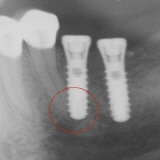

- Fehlerhafte Positionierung der Implantate